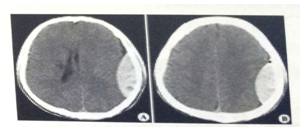

男55歲,左側(cè)肢體偏癱4小時(shí),有高血壓史,診斷為

A.急性硬膜下血腫

B.急性硬膜外血腫

C.顱骨骨折

D.急性腦梗死

E.急性腦出血

【答案】E